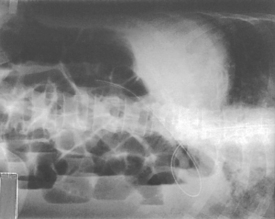

The air-barium distribution within the stomach and large intestine changes with various body positions. By knowing these distribution patterns, one can determine in which body position a radiograph was taken. Air always rises to the highest levels, and the heavy barium settles to the lowest levels (air is black, barium is white).

The fundus is located more posteriorly; therefore in the supine position it would be the lowest portion of the stomach and would be filled with barium.

In both prone and erect positions, the fundus would be filled with air as seen on the drawings below, with a straight air-barium line on the erect.

The ascending and descending portions are located more posteriorly, and thus more of these parts in general would be filled with barium (white) in the supine position and with air (black) in the prone position.

This much separation of barium and air occurs generally only with double-contrast barium-air studies.

Air-fluid levels would be seen in the erect position in which the air would rise to the highest position in each of the various sections of the large intestine, as shown in the accompanying figure.